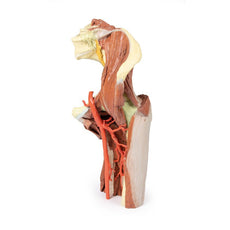

The inguinal region and perineum

A distinctive and unique feature of this model is the dissection of

simultaneous direct and indirect hernias preserved on the right and left sides, respectively. While most of the

anterior abdominal wall has bee removed, the inferior epigastric arteries (and accompanying veins) have been

retained to allow for interpretation of the herniations. On the right side, a distinct outpouching of the

parietal peritoneum has formed medial relative to the inferior epigastric artery, representing an indirect

herniation event. On the left side, the hernia sac extends laterally relative to the inferior epigastric artery

and into the opened spermatic cord, with continuity of the epiploic appendage from the sigmoid colon into the

sac.

The thigh

Anterior dissections into the femoral triangle region have been undertaken to both thighs with

varying preservation of contents. On the right side the femoral sheath has been removed to expose the femoral

artery, vein and the deep inguinal lymph nodes. The femoral artery has been sectioned with a portion removed to

expose the origin of the profunda femoris and to better appreciate the draining of the great saphenous vein into

the femoral vein. Just lateral to these structures the very terminal component of the femoral nerve is visible.

On the left side a slightly larger dissection window has been opened to expose more of the underlying anterior

and medial thigh compartment muscles, from the sartorius and iliopsoas laterally to the pectineus and adductor

longus medially. The femoral artery has been preserved, with a well-preserved superficial circumflex iliac

artery and the origin of the profunda femoris visible adjacent to the femoral nerve.

The model terminates at

the level of the mid-thigh, and while not a primary focus of the model the spatial organisation of structures in

the cross-section can be seen. This includes the anteriorly positioned femoral diaphysis with tightly-packed

anterior compartment muscles and the passage of the femoral artery and vein in the subsartorial canal.